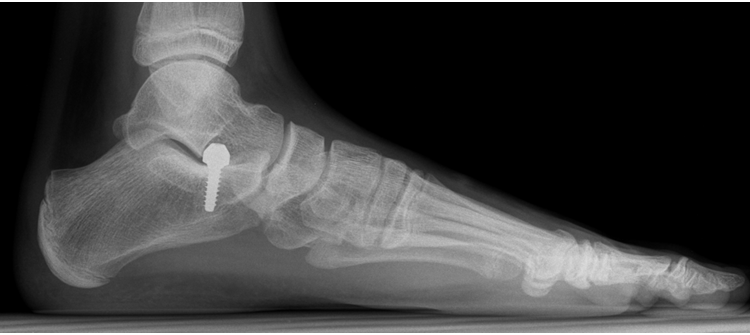

القدم المنحرفة قبل التصحيح

أنهى أطباء جراحة العظام والمفاصل في مستشفى “بريدة المركزي” (وسط السعودية) معاناة مريض كان يشكو من انحراف بالقدم وعدم ثبات وضعية المفصل أثناء الحركة، تسبّب له بحدوث ألم شديد ومزمن في مفصل الكاحل والقدم اليمنى منذ 10 سنوات. وفي بيان لوزارة الصحة السعودية، فإن المريض حضر إلى عيادة العظام بالمستشفى يوم 12 أيلول (سبتمبر) الماضي بعد تزايد حدة الألم الذي يعانيه، اثر تعرّضه لإصابة قديمة ألحقت ضرراً بوتر “Flat foot” . وللحال أجريت الفحوص اللازمة وبينها الأشعة المقطعية، فتبيّن أن لدى المريض حالة تفطح بالقدم اليمنى. عندها قرّر إجراء عملية جراحية تحت التخدير الكلي تمّ خلالها تعديل اعوجاج الكعب بواسطة مسامير مجوّفة، وهو ما أدّى الى تطويل الجزء الخارجي للقدم، بعد وضع رقعة عظمية تمّ أخذها من الحوض، وتقصير الجزء الداخلي للقدم، وتطويل “وتر أكيليس”. كما تم تنفيذ عملية نقل أوتار حول القدم، وكذلك تهذيب الوتر القديم المصاب، وتثبيته بواسطة بواسطة مسمار ذاتي الذوبان.

التدخل الجراحي المشار اليه تكلل بالنجاح، وفق بيان للفريق الطبي المعالج، بدليل تحسّن حالة المريض الذي غادر بعدها المستشفى بصحة جيدة مع المتابعة في العيادات الخارجية. وقد عدّ هذا الإجراء الجراحي من أوائل العمليات الجراحية في هذا المجال.